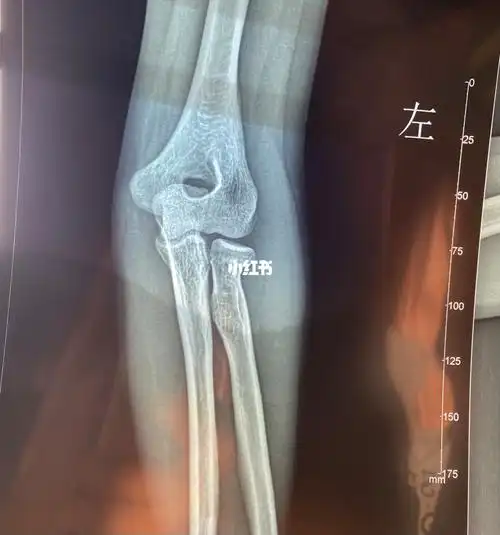

桡骨骨折